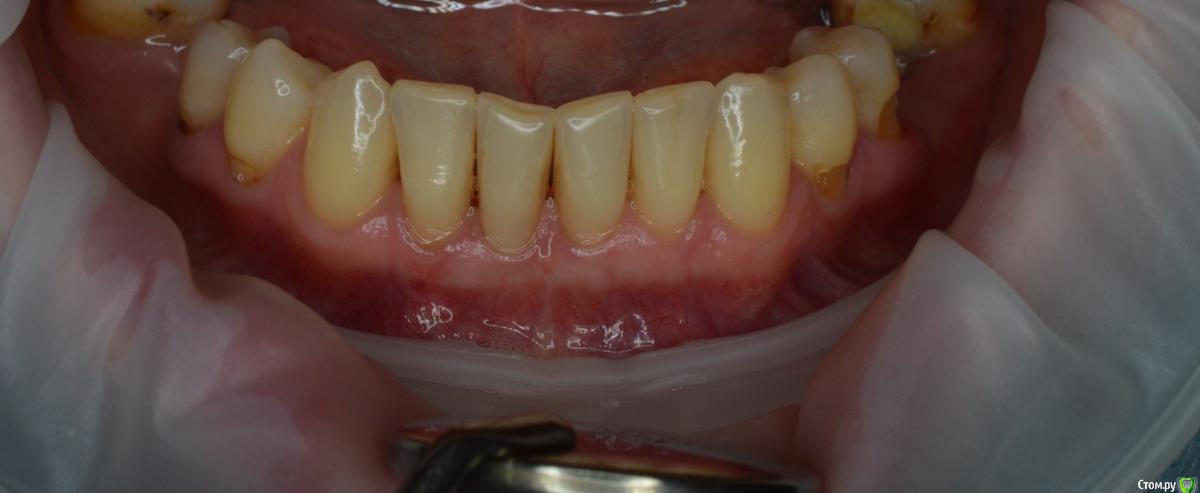

Dr.Safiullin Опубликовано 12 мая, 2017 Поделиться Опубликовано 12 мая, 2017 (изменено) Добрый вечер всем, решил тоже свой первый, небольшой кейс выложитьСильно не ругайте, полгода как получил диплом) Вопрос: 1)Нужно ли подшивать губу? Я не подшил, потому что в гос. времени мало на приём, да и испугался надкостницу травмировать лишний раз. А то боялся получить рубец, хотя не получил его!) 2) на 5 фотке это десквамация? Приветствуются конструктивная критика! Спасибо Изменено 12 мая, 2017 пользователем Dr.Safiullin Ссылка на комментарий

Dr.Safiullin Опубликовано 13 мая, 2017 Автор Поделиться Опубликовано 13 мая, 2017 Доктор, вы прекрасно провели ненужную и бесполезную операцию )) Тут не было показаний для вестибулопластики.Может быть, но а как же преддверие 1.5-2мм, тонкий биотип десны, рецессия по 3 классу по Миллеру в области фронтальных зубов? Из за скученность тоже убыль, но все же. Вот тут может быть информативнее будет Ссылка на комментарий

колесников Опубликовано 13 мая, 2017 Поделиться Опубликовано 13 мая, 2017 (изменено) Прелестное было преддверие. Обратить внимание следовало на особенности прикуса, выявить в анамнезе бруксизм, местно -суперконтакты. Думаю причина рецессии в перегрузке.Кстати подшивать лоскут надо было к кератинизированой слизистой,тогда не было бы диссонанса в цвете в виде зебры ,в окончательном варианте Изменено 13 мая, 2017 пользователем колесников Ссылка на комментарий

Bier Опубликовано 13 мая, 2017 Поделиться Опубликовано 13 мая, 2017 у зубов по 2мм кератинизированной десны. Причина не в ее дефиците. Преддверие было нормальным. Ссылка на комментарий